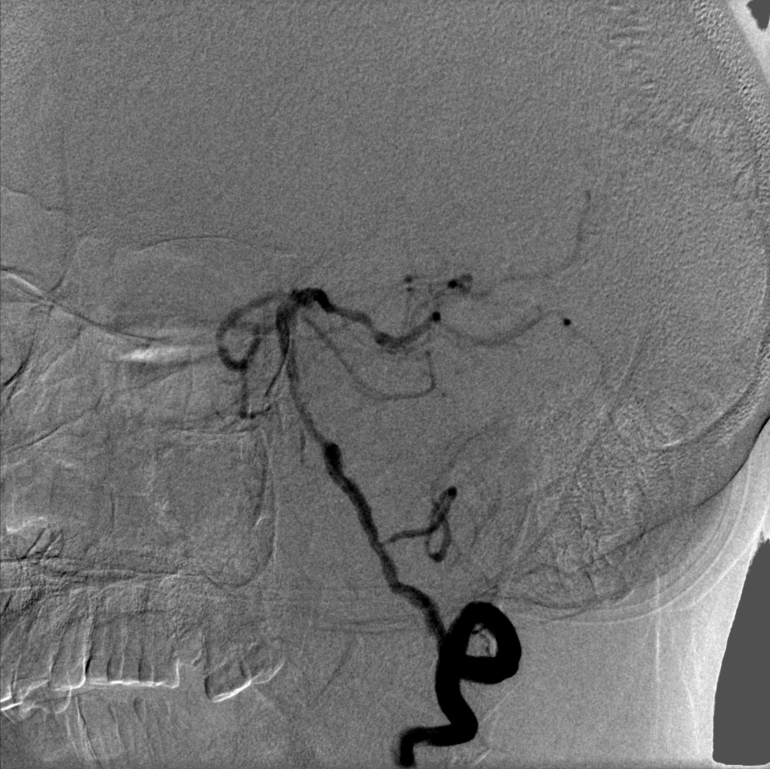

2022-10-11我院头颈DSA:

➤ 主动脉弓造影:Ⅰ型主动脉弓,右侧锁骨下动脉迂曲。

➤ 左侧颈内动脉造影:左侧颈内动脉C1段局限性狭窄约90%,C4-6段斑块形成,左侧大脑中动脉下干M2段狭窄约50%。

➤ 右侧颈内动脉造影:右侧颈内动脉C4段局限性膨大,溃疡斑块形成,C5段狭窄约50%。